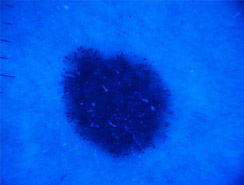

Dermatoscopia

Lo studio e la diagnosi delle neoformazioni cutanee attraverso strumenti specifici indicati per un'analisi delle caratteristiche strutturali superficiali e profonde delle varie neoformazioni cutanee: dermatoscopia, dermalite a luci fotocromatiche, mappatura nevica con videodermatoscopia digitale.

Al fine di una corretta diagnosi dei nevi, e dunque di un'efficace prevenzione da forme tumorali, è indispensabile visionare in profondità i caratteri di ogni formazione nevica. Ciò è reso possibile dall'utilizzo del dermatoscopio e dalla concomitante mappatura nevica, con l' eventuale rimozione chirurgica o laser di: